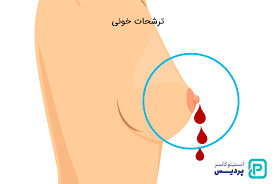

قیمت: 68٬000 تومان - دسته بندی فایل: پاورپوینتپاورپوینت تشخیص بیماری سرطان سینه با استفاده از تکنیک های داده کاوی

فروش ویژه پاورپوینت حرفه ای تشخیص بیماری سرطان سینه با استفاده از تکنیک های داده کاوی با تخفیف استثنایی فقط 43 هزار تومان تعداد اسلاید: 34 اسلاید